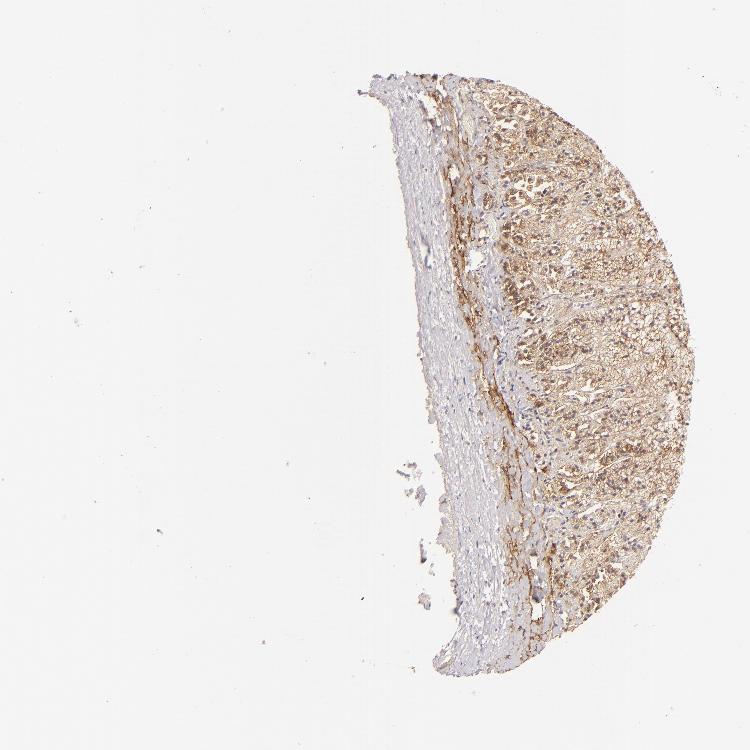

ADRENAL GLAND - Antibody stainingi

Antibody staining in the annotated cell types in the current human tissue is reported as not detected, low, medium, or high, based on conventional immunohistochemistry profiling in selected tissues. This score is based on the combination of the staining intensity and fraction of stained cells.

Each image is clickable and will lead to virtual microscopy that enables deeper exploration of all samples and also displays staining intensity scores, fraction scores and subcellular localization as well as patient and tissue information for each sample.

Antibody HPA048319Antibody CAB002602

Glandular cells LowMedium